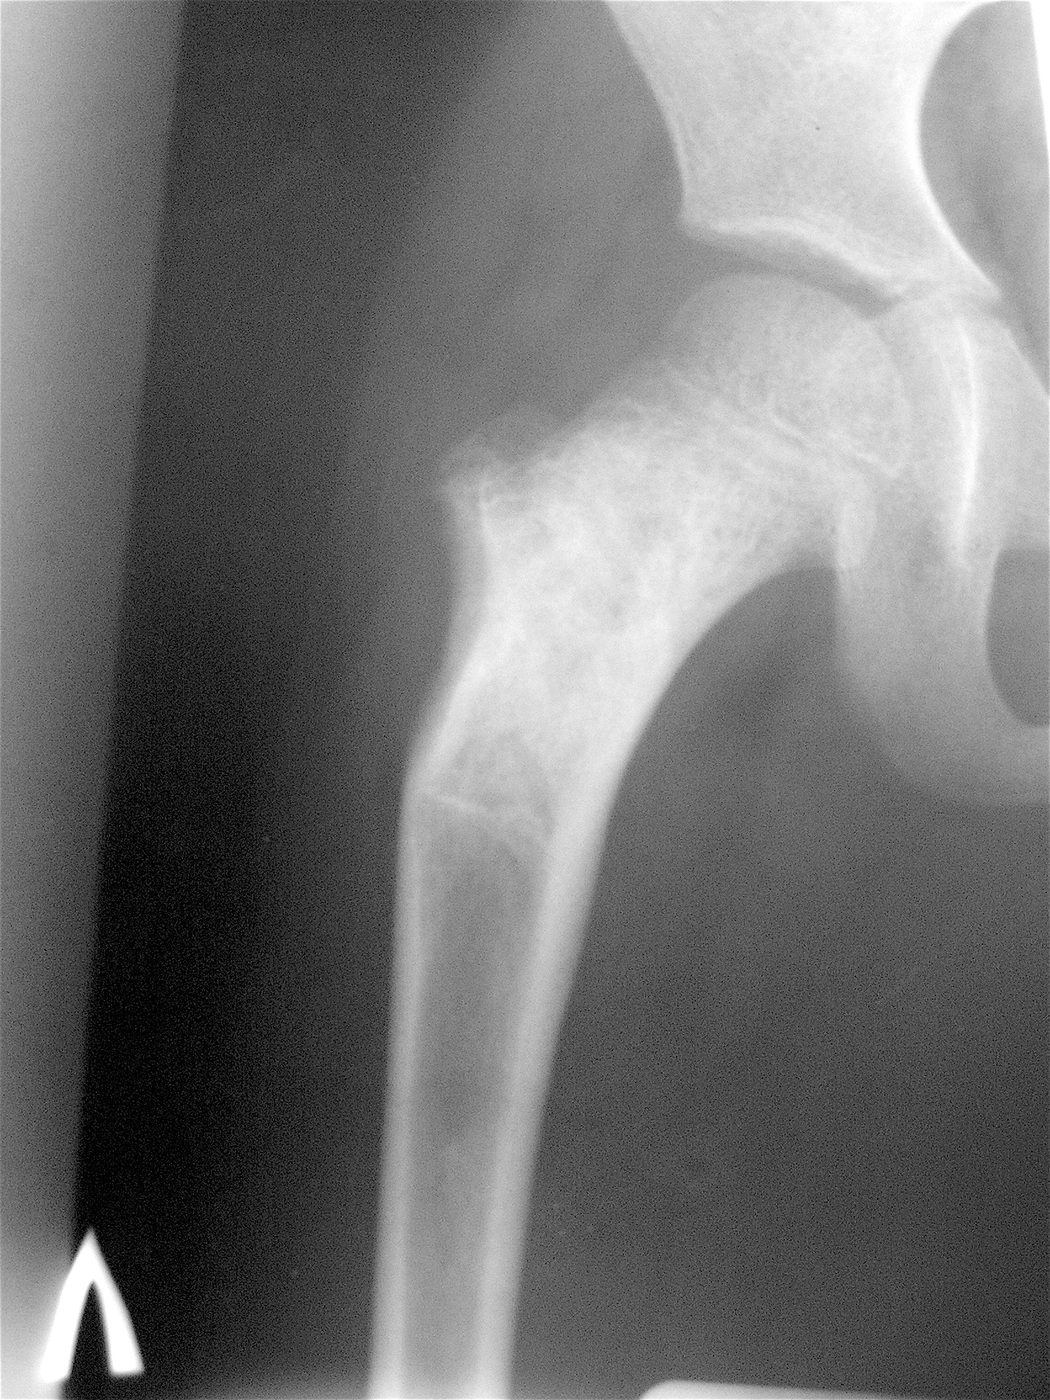

Закрытый патологический перелом шейки левой бедренной кости и проксимального метафиза бедренной кости на фоне аневризмальной костной кисты.

Аллопластика материалом «Лиопласт».